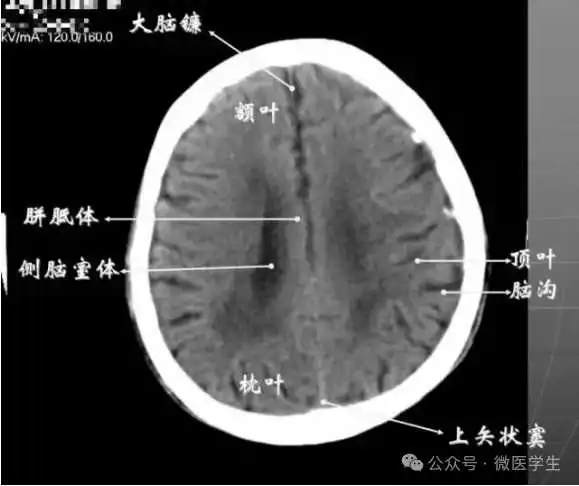

九面:听眦蝶鞍三下上体顶卵园灰质象1.听眦线层面(00mm)2.蝶鞍层面(+10mm)3.鞍上池层面(+20mm)4.三脑室下部层面(+30mm)5.三脑室上部层面(+40mm)6.侧脑室体部层面(+50mm)7.侧脑室顶部层面(+60mm)8.半卵圆中心层面(+70mm)9.灰质层面(+80mm)

内侧壁侧脑室体部被胼胝体分开,侧脑室体部的外方为顶叶,顶枕沟及中央沟将大脑为为额、顶、枕叶。

在胼胝体和侧脑室上方,大脑镰自前向后贯穿中线。白质部分为半卵圆中心,额叶范围缩小,顶叶所占比例扩大,枕叶基本消失。

- 半卵圆中心:位于胼胝体上方,由左右大脑半球髓质形成的有髓纤维,对称位于大脑镰两侧区域。